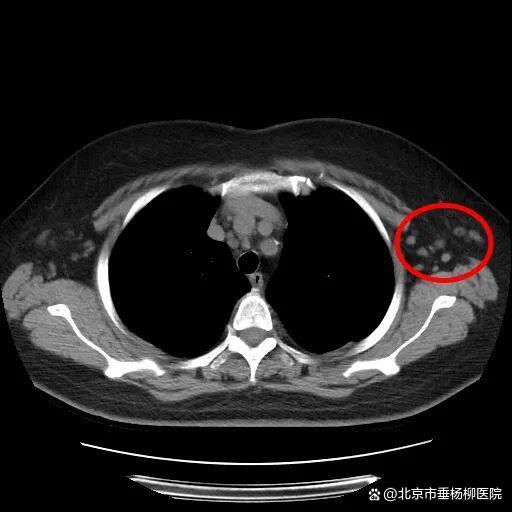

来到清华大学附属垂杨柳医院感染性疾病科后,副主任医师王同德接诊了该患者,并完善了相关检查,初步结果提示其血尿化验基本正常,流感及新冠抗原检测为阴性,胸部CT未见肺炎表现,但影像提示左侧腋窝淋巴结肿大。

▲红圈处可见肿大淋巴结